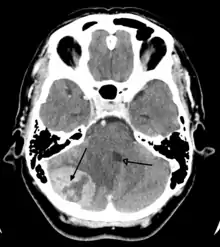

A posterior fossa tumor leading to mass effect and midline shift

Although there is no specific or singular symptom or sign, the presence of a combination of symptoms and the lack of corresponding indications of other causes can be an indicator for investigation towards the possibility of a brain tumor. Brain tumors have similar characteristics and obstacles when it comes to diagnosis and therapy with tumors located elsewhere in the body. However, they create specific issues that follow closely to the properties of the organ they are in.[40]